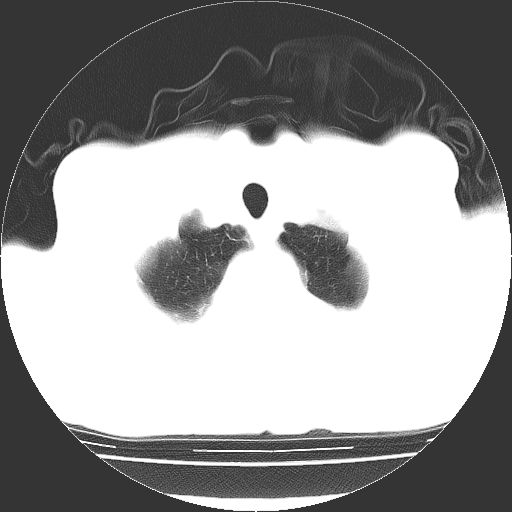

以下是引用hhcckk在2009-1-1 15:38:00的发言:[br]左下肺少许絮状模糊影--考虑感染[br]两肺散在小点状密度增高影--结合病史考虑矽肺?[br]气管壁钙化--可能由于老年退变性引起的